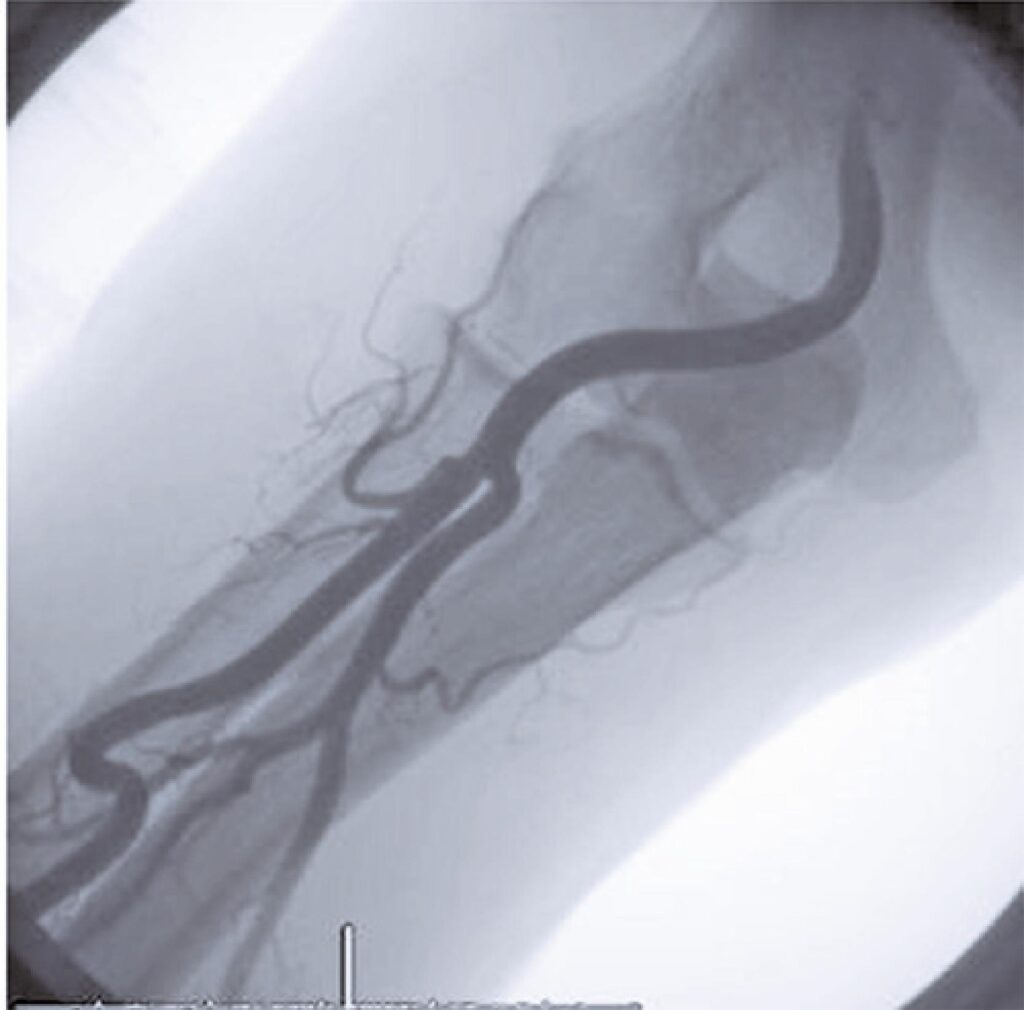

Through the efforts of dedicated interventionists, catheterization of the cardiovascular system by transradial method has been recognized as the gold standard due to the several advantages associated with it, such as early ambulation, decline in bleeding and in various other vascular complications. It has successfully turned as an alternative to femoral access. The huge experience of interventionists has helped in understanding the anatomical impediments that can result in many technical issues and complications associated with the transradial approach. A trial-and-error method adopted by the interventionists on their learning curve at the cost of increased procedural failure, complications and patient inconvenience may not be justifiable. The objective of the present manuscript was to review all these difficulties, and understand the treatment method and various preventative strategies that can be used to overcome the complications.